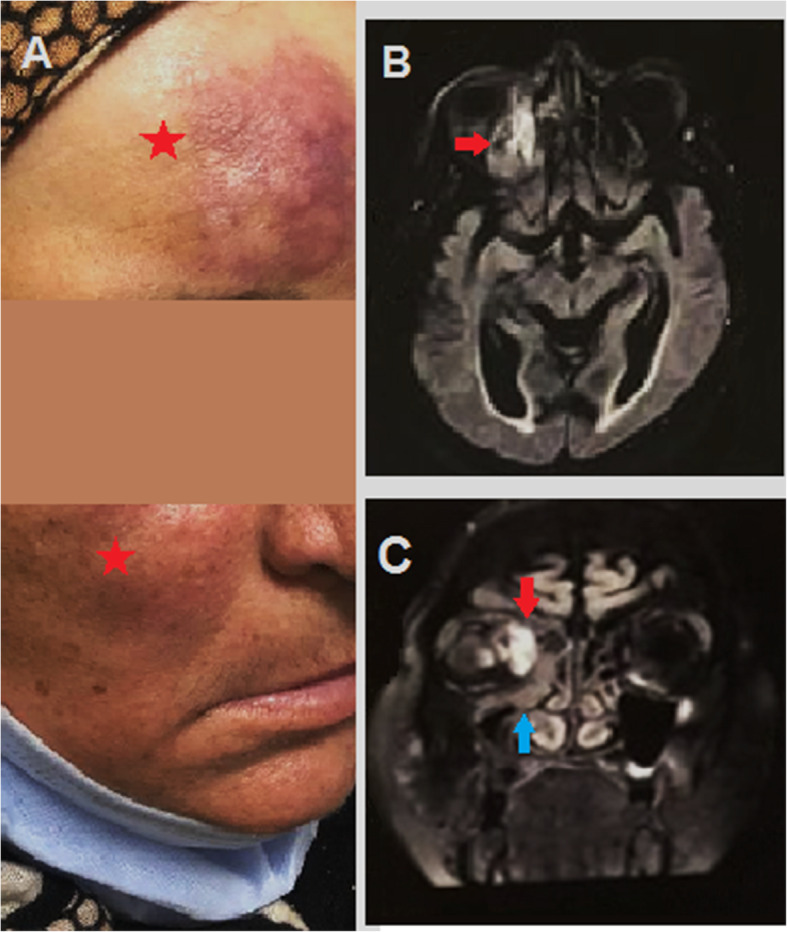

An elevated skin lesion with dark discoloration along the forehead and right cheek as well as decreased sensation along maxillary division of trigeminal nerve was noted (Fig. 1A).

Fig. 1.

A Red star highlighting elevated dark colored forehead and right cheek that goes with cutaneous form of mucormycosis. B Red arrow along axial MRI with obliteration of right ostiomeatal complex. C Red arrow along coronal MRI revealing obliteration of right ostiomeatal complex with infiltration of infection to the right orbital cavity. Blue arrow showing maxillary, ethmoid and frontal sinusitis all around the right orbital cavity

Magnetic resonance imaging (MRI) brain and magnetic resonance venography (MRV) with cavernous view as well as MRI orbit with contrast on a 1.5 Tesla super conductive system revealed diffuse enhancement mucosal thickening, along the right maxillary, ethmoidal, and frontal sinuses with occlusion of the right ostiomeatal complex, retro-orbital diffuse edema with faint enhancement, chronic small vessel disease, and intact venous system with no filling defects (Fig. 1B, C).